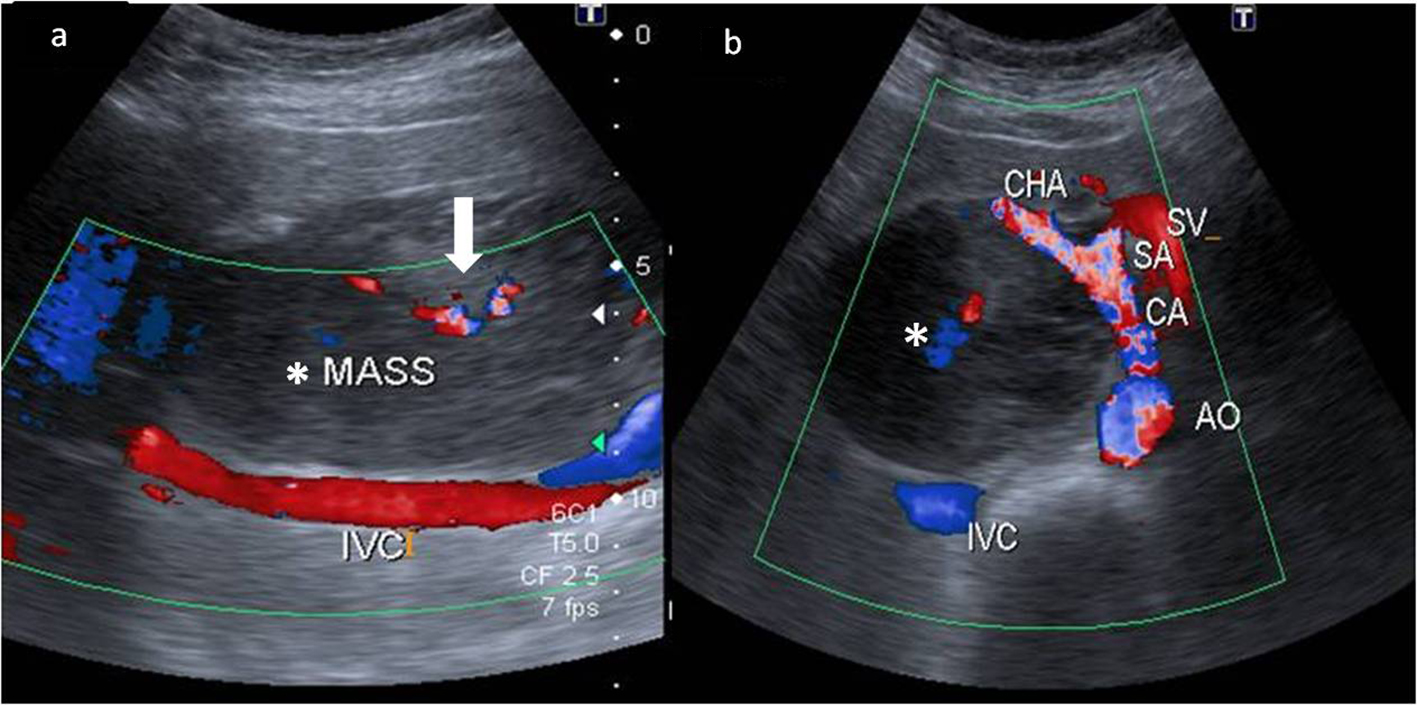

A 43-year-old female presented to our hospital with the complaints of progressive pain abdomen for 3 months. Abdominal pain was unrelated to food intake and was constant, dull-aching in nature. No lump was palpable on clinical examination and the abdomen was non-tender. Laboratory investigations including hematological and liver function tests were normal. On the basis of the above physical assessment, the patient was referred for cross-sectional imaging- sonography of the abdomen, to evaluate the cause of pain. The investigation revealed a hypoechoic retroperitoneal mass sandwiched between the pancreas anteriorly and the aortocaval region posteriorly, encasing the origin of common hepatic artery (Fig. 1a, b). The patient further underwent a contrast-enhanced computed tomography (CECT) scan on a 64-slice CT scanner (Discovery750HD, General Electric, GE Healthcare, USA) to characterize the mass. CECT was performed by injecting 100 mL of intravenous contrast iomoperol (Iomeron, Bracco, Germany) using a pressure injector with bolus tracking technique and a dynamic triple phase study through an 18-gauge needle in the ante-cubital vein at a rate of 4 mL/s. In addition to a baseline non-contrast study, images were acquired during arterial phase (20 s), venous phase (70 s) and equilibrium phase (180 s). Thin reformatted and multiplanar images were studied before arriving at a differential diagnosis for the mass. The above CECT scan revealed a heterogeneously enhancing, lobulated solid mass lesion in the retroperitoneum with internal non-enhancing liquefied/necrotic areas anterior to the aortocaval region. The enhancement was persistent but equivalent to the phase of the dynamic study. The mass was seen to encase the celiac axis and its branches at their origin with extension along the common hepatic artery (CHA) for a small segment after origin (Fig. 2a) and along the hepatoduodenal ligament towards porta hepatis. It was seen to abut and partially encase the superior mesenteric artery (SMA) with circumferential contact of 180° (Fig. 2b) as well as compress and displace the main portal vein (Fig. 2c). The mass was seen to cross the mid line towards the left side in the pre-aortic location (Fig. 2d). Mass effect on the common duct was present with resultant minimal central bilobar intrahepatic biliary radicles dilatation. Fat planes with other neighboring structures such as caudate lobe of liver, right adrenal gland and the inferior vena cava (IVC) were maintained. There was no evidence of calcification within the tumor bulk. Based on the above features of soft tissue extension and insinuation along the retroperitoneal structures and partial encasement without obvious thrombosis of the affected vessels within the abdomen, a differential diagnosis of lymphoma or retroperitoneal mesenchymal tumor was made.

![]() Click for large image | Figure 1. Color Doppler images of the mass (*) in the retroperitoneum. (a) Extent of the mass anterior to the inferior cava (IVC) with minimal color flow within it (white bold arrow). (b) The hypoechoic mass (*) compressing and splaying the celiac axis (CA) at its origin from the aorta (AO). The common hepatic artery (CHA) is also seen being splayed by the mass. The splenic artery (SA) and the splenic vein (SV) are in close proximity to the mass but appear spared. |

Till date, only 60 cases of primary EGIST of the retroperitoneum have been reported so far [3]. The objective of presenting our case of primary retroperitoneal EGIST was to highlight its clinical presentation and imaging characteristics along with the disease course showing rapid progression despite aggressive imatinib therapy. In our patient, the clinical onset of disease was insidious over a period of 3 - 4 months with increasing abdominal pain, since the mass was extraluminal in location. The pain was likely due to the neuro-vascular encasement by the mass as demonstrated in the retroperitoneum (Figs. 1a and 2a).